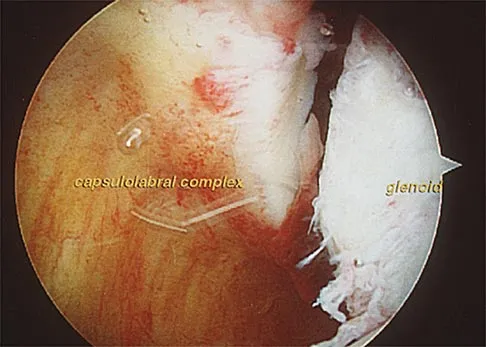

In patients older than age 40 years who sustain a first-time anterior dislocation of the shoulder, prolonged morbidity is most commonly associated with

Explanation

In the study done by Pevny and associates, 35% of patients older than age 40 years sustained rotator cuff tears and 8% had axillary nerve palsies. All of the patients with axillary nerve palsy also had rotator cuff tears. Imaging of the rotator cuff is indicated in this age group. The incidence of recurrent instability in patients older than age 40 years is 10% to 15%. Pevny T, Hunter RE, Freeman JR: Primary traumatic anterior shoulder dislocation in patients 40 years of age and older. Arthroscopy 1998;14:289-294. Sonnabend DH: Treatment of primary anterior shoulder dislocation in patients older than 40 years of age: Conservative versus operative. Clin Orthop 1994;304:74-77.